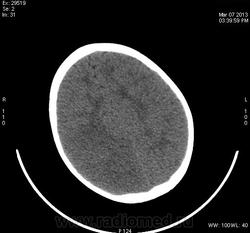

Предположу снижение плотности в правой лобно-теменно-височной области - инсульт в бассейне правой СМА?

Теменная, затылочная справа, ишемический инсульт. С бассейна СМА, как мне видится, "залезает" на бассейн ЗМА, - возможно, вариант развития виллизиева круга.